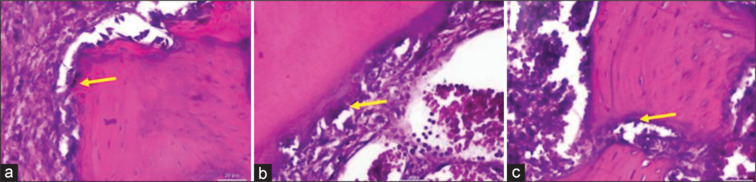

Materials and methods: Thirty-six Wistar rats were randomly divided into three groups: rat sockets were given a 1 mm × 1 mm × 1 mm HAGP scaffold, rat sockets were given a 1 mm × 1 mm × 1 mm HAGP-CS, and a control group (rat sockets were not given scaffold material). Following lower left molar extraction, scaffold materials were applied to the sockets. Assessments were conducted on days 7th, 14th, and 28th, with osteoblast counts determined via hematoxylin-eosin staining, and ALP and OCN expressions were analyzed using immunohistochemistry (IHC) staining.

Results: A significant increase in osteoblast count was observed on day 28 (P = 0.001). In addition, significant differences were noted in ALP expression on day 7 (P = 0.030) and day 28 (P = 0.001), as well as in OCN expression on days 7 and 28 (P = 0.001) across the groups.

Conclusions: Administering a HAGP-CS scaffold significantly enhances osteoblast proliferation and increases ALP and OCN expression in the alveolar bone rat model.